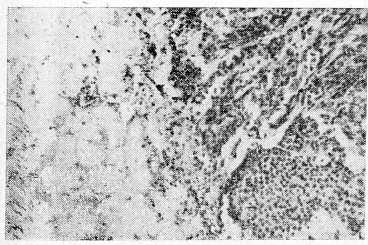

При микроскопическом исследовании оказалось, что опухоль перикарда построена из полиморфных, в основном мелких клеток с неправильной формы крупными, плотными ядрами (рис. 2).

В печени опухоль представлена крупными светлыми полигональными клетками с пузырьковидными ядрами. Хорошо выражена соединительная строма (рис. 3). В надпочечниках обнаружены метастазы рака печени; они же имелись в части лимфатических узлов, в других узлах найдены метастазы мезотелиомы.

Рис. 3. Опухоль печени. Справа печеночная ткань, инфильтрируемая опухолевыми клетками. В центре левой половины участок опухоли трабекулярного строения. Гематоксилин-эозин. X 200.